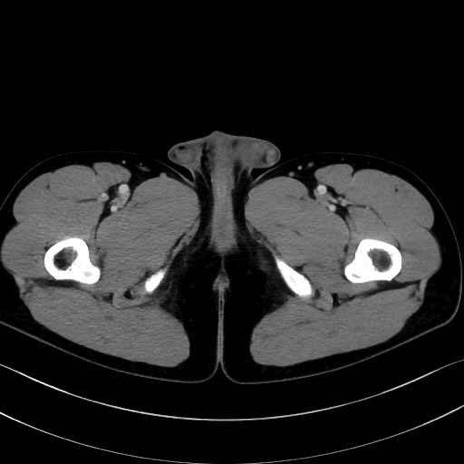

肛門挙筋 (Levator ani)